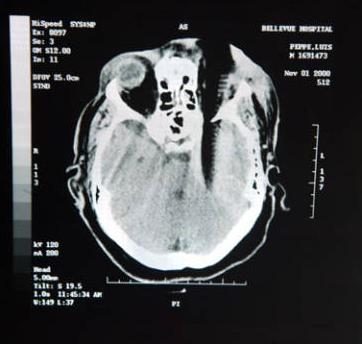

Comb stabbed in the skull

X-ray of Louis Pepe, when he was stabbed by comb in the skull last 2000. He lost his left eye and affected his right eye as well. The comb caused him much damage paralyzing his right arm and leg and his ability to speak. The attacker was sentenced 23 years imprisonment.